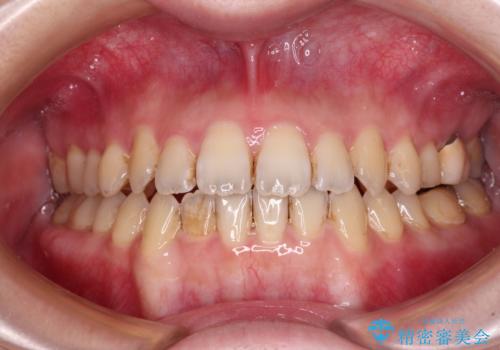

オープンバイトと前歯のデコボコをインビザライン矯正で解消

- 前歯の開咬を気にして来院された患者様です。

開咬の治療は、前歯を閉じるように動かすとともに、上下臼歯を圧下(骨内にめり込ませる)させることで進めて行きます。

インビザラインは臼歯の圧下を効果的に行えるため、インビザラインを用いて矯正治療を行うこととしました。